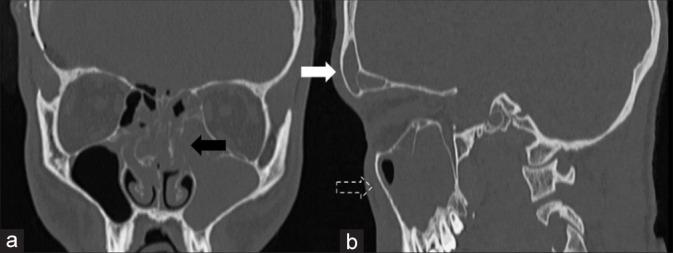

Spontaneous and nontraumatic epidural hematoma (SEDH) is a rare entity. Etiology is various, including vascular malformations of the dura mater, hemorrhagic tumors, and coagulation defects. The association between SEDH and craniofacial infections is rather unusual.

A total of 18 scientific publications, corresponding to 19 patients, met the inclusion criteria for the qualitative and quantitative analysis. Patients were mostly adolescents, with a clear male predominance. SEDHs frequently occurred in the frontal area, usually near the site of the infection. Surgical evacuation was the treatment of choice with good postoperative outcomes. Endoscopy of the involved paranasal sinus should be achieved as soon as possible to remove the cause of the SEDH.

自发性非创伤性硬膜外血肿(SEDH)是一种罕见的病症。病因多种多样,包括硬脑膜血管畸形、出血性肿瘤和凝血缺陷。SEDH与颅面感染之间的关联相当罕见。

共有18篇科学出版物,对应19例患者,符合定性和定量分析的纳入标准。患者大多为青少年,男性明显占主导。SEDH常发生在额叶区域,通常靠近感染部位。手术清除是首选治疗方法,术后效果良好。应尽快对受累鼻窦进行内镜检查以消除SEDH的病因。